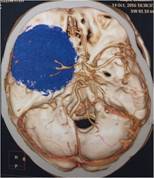

经查体,神经外六科吴杰主任诊断为:左侧蝶骨嵴占位性病变,考虑脑膜瘤可能性大。之后黄女士完善了相关检查,颅脑CT及CTA检查提示:左侧中颅窝底巨大占位病变,其内血管丰富,临近左侧大脑中动脉明显受压向上移位,考虑脑膜瘤;颅脑磁共振提示:左侧前中颅窝底巨大占位性病变,考虑脑膜瘤。介入栓塞提示:肿瘤主要由左侧脑膜中动脉额支、少量由左侧眼动脉脑膜支参与供血。

颅脑CT及CTA检查可见左侧额颞稍高密度占位,肿瘤血供丰富